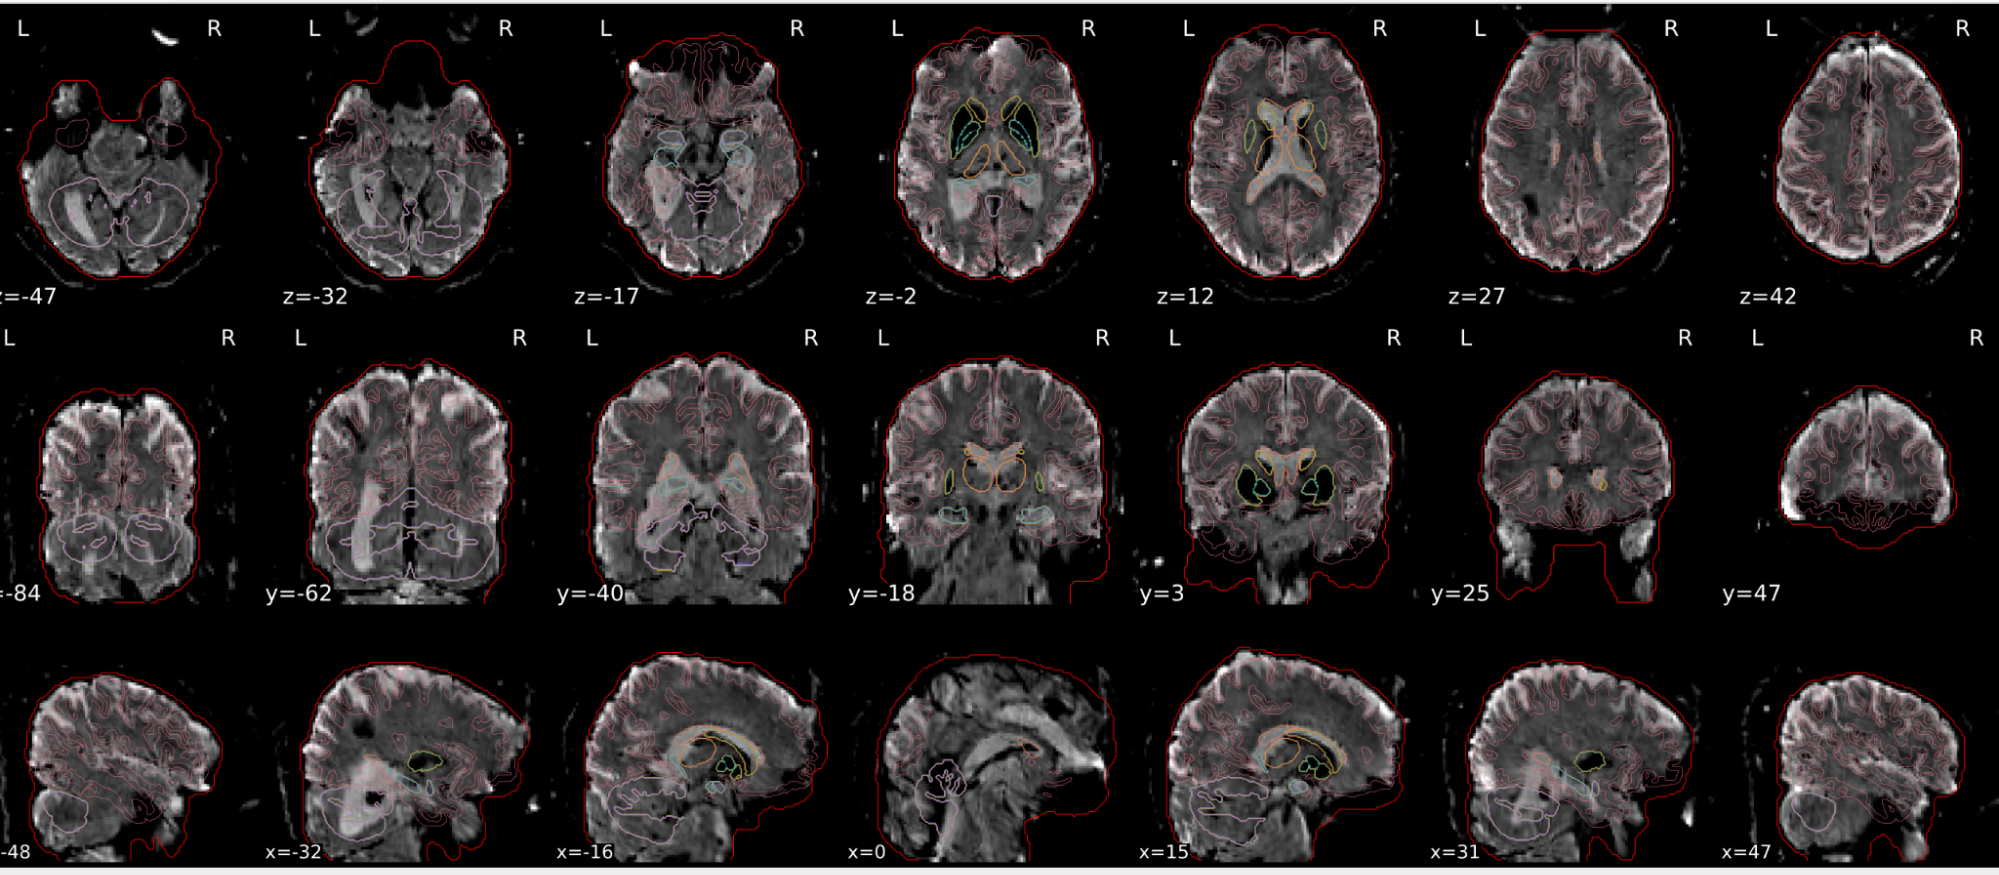

EPI spatial normalisation

This QC step shows the registration of the EPI image to MNI space.

Example of a good subject

- If the registration performed well, you should see an overlap (i.e., correspondence of structures) between the MNI template and the EPI registered to the MNI space.

- If parts of the brain are missing due to the scanner field of view, this is fine. For example, the cerebellum may be cut off for a participant with a large head.

Example of a bad subject

- In case of poor registration, you should see a misalignment of the EPI and the MNI template

Summary

| good | bad |

|---|---|

| Overlap (i.e. match of structures) between the MNI template and the EPI registered in the MNI space | Misalignment of the EPI and the MNI template |

| If parts of the brain are missing because the field of view of the scanner is limited, the EPI spatial normalisation does not have to be excluded e.g. cerebellum cut off in person with large head |

If parts of the brain are missing because the field of view of the scanner is limited, the EPI spatial normalisation does not have to be excluded (e.g. cerebellum cut off in person with large head)